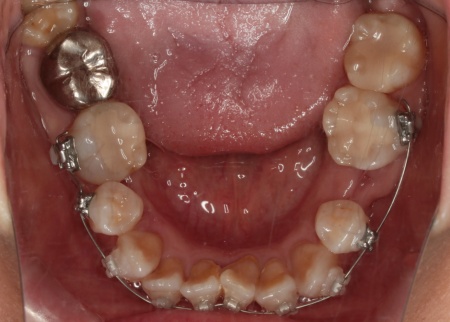

治療後